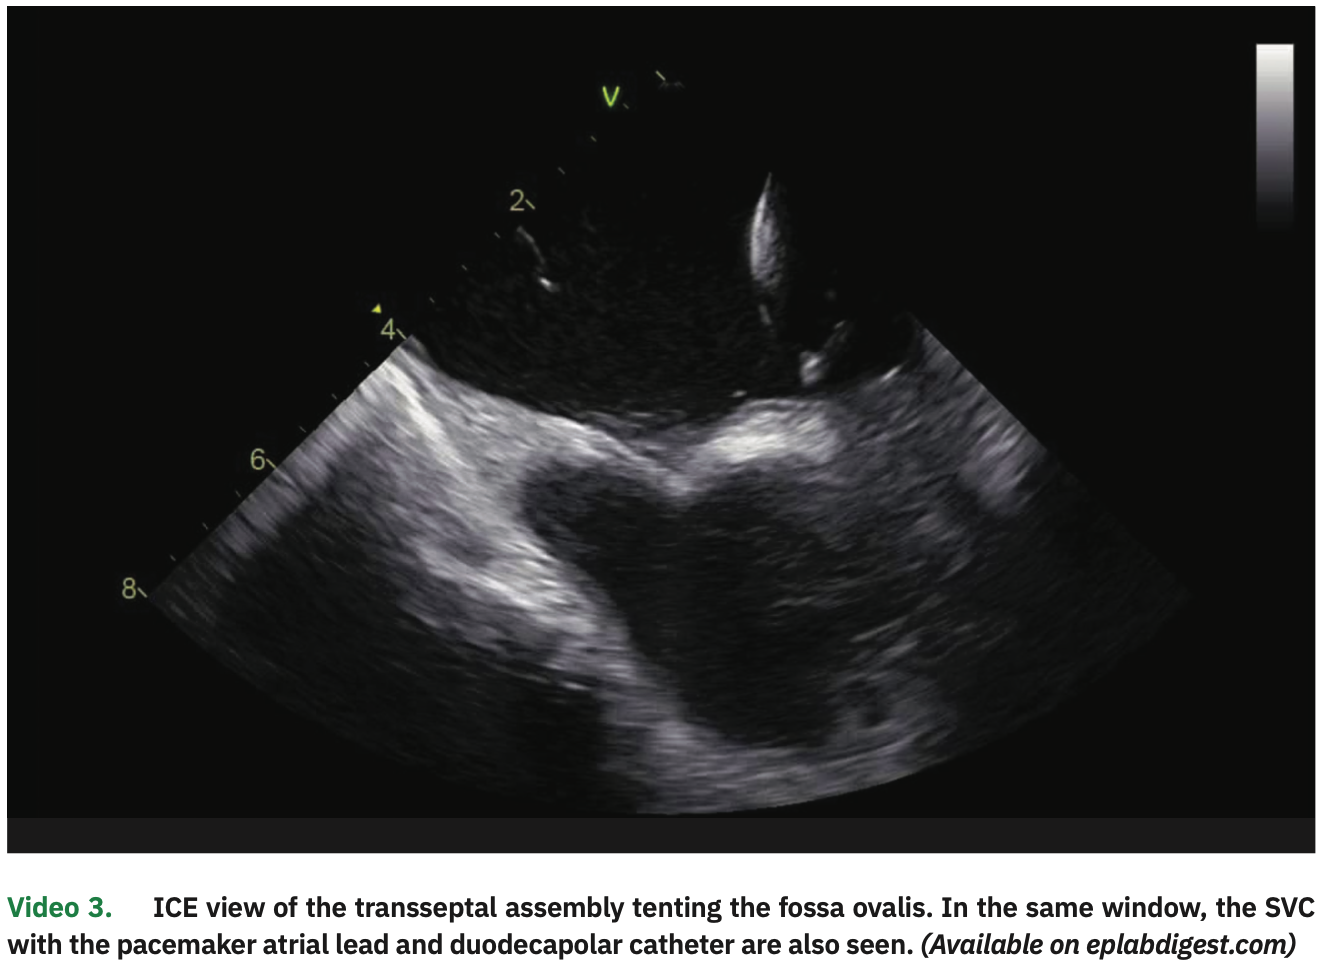

Two transseptal punctures were separately performed under ICE visualization, coming down to the septum from the SVC (Figure 3 and Video 3). After each septal perforation, a guidewire was advanced to the left superior pulmonary vein (LSPV), thus allowing for safe over the wire sheath positioning in the left atrial (LA) cavity. The ablation catheter and a multipolar spline catheter were then positioned in the PVs. All these steps were clearly visualized on ICE.

In particular, ICE visualization is key in every step of the way. We are even promoting a new hashtag on social media for this (#ICEeyes), since ICE is our “eyes” to see what we are doing. With thorough ICE scanning, all the steps can be adequately monitored, even as catheters come out of the sheath tip (making sure it does not force on the atrial wall). There is no blind step using this approach, even when advancing catheters or wires in the venous system to the heart. CS visualization and cannulation are better than with fluoroscopy. Transseptal punctures are also undoubtedly best visualized on ICE. A short learning curve is required to become comfortable and proficient in ICE manipulation; however, we feel that ICE definitively provides better and more detailed information than fluoroscopy.